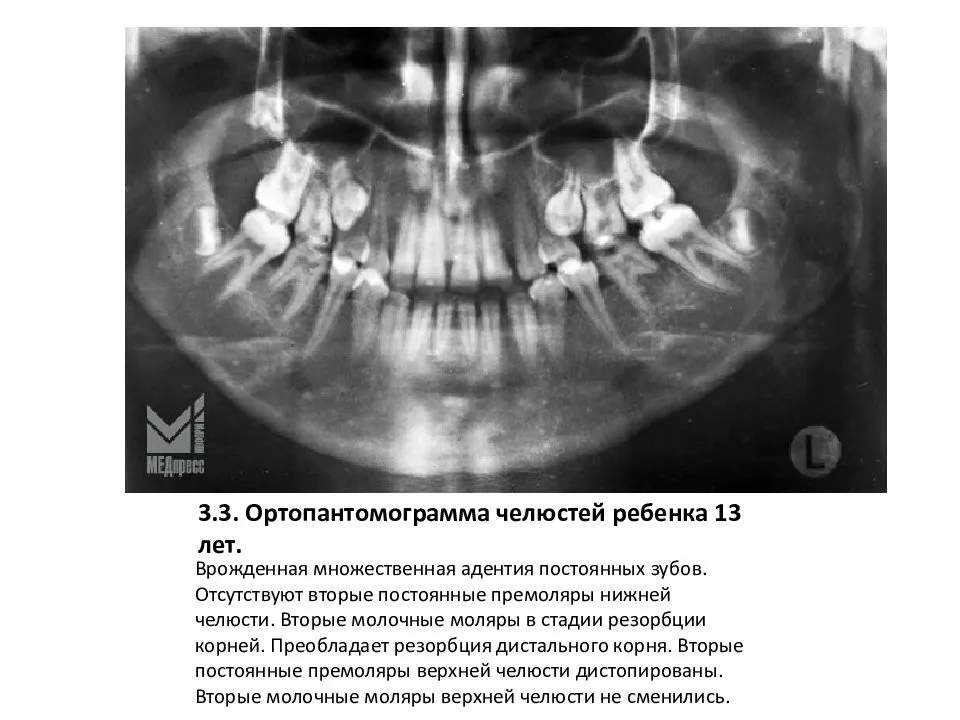

Примеры ортопантомограмм и их анатомия

Раздел: Фотоэссе